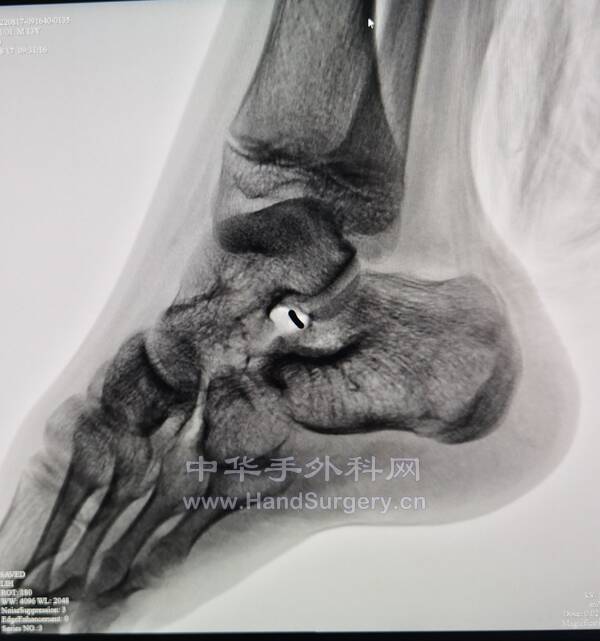

今日参与手术2台注意事项:

1.距骨囊肿:根据囊肿位置确定切口,显露距舟关节,观察关节面情况,如果可保留关节面,行切除植骨,如果不能保留,行距舟关节融合。